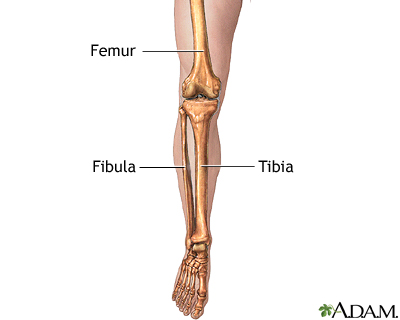

what are the bones of the lower leg?

tibia

fibula

which of the lower leg is the major weight bearing bone?

tibia

how much weight does the fibula bear?

about 10% of body weight